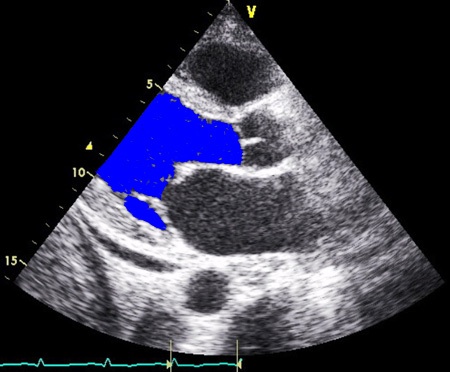

QCM ECHOCARDIOGRAPHIE --- Introduction ---

Module de QCM proposé par le service de Réanimation Médicale du CHU de Nice à l'intention des étudiants du DCEM pour apprendre les Bases de l'ECHOCARDIOGRAPHIE.